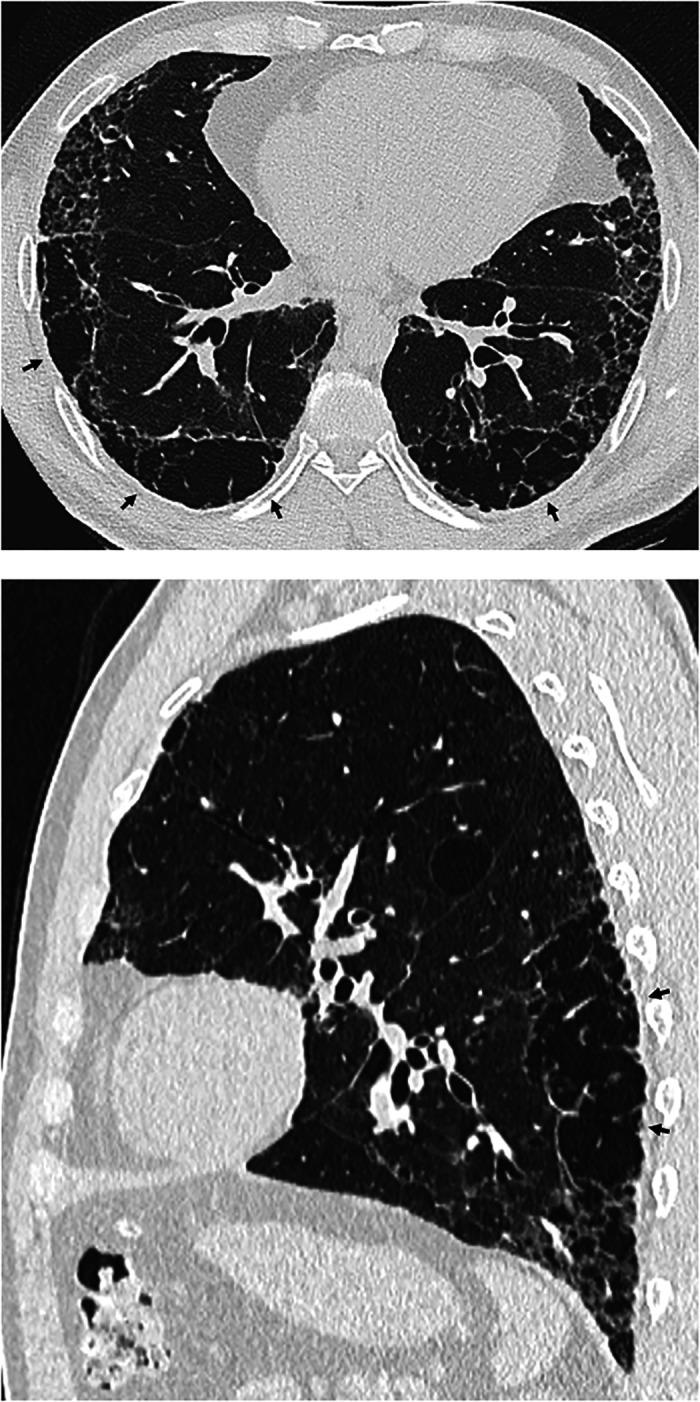

This American Thoracic Society, European Respiratory Society, Japanese Respiratory Society, and Asociación Latinoamericana de Tórax guideline updates prior idiopathic pulmonary fibrosis (IPF) guidelines and addresses the progression of pulmonary fibrosis in patients with interstitial lung diseases (ILDs) other than IPF. A committee was composed of multidisciplinary experts in ILD, methodologists, and patient representatives. ) Update of IPF: Radiological and histopathological criteria for IPF were updated by consensus. Questions about transbronchial lung cryobiopsy, genomic classifier testing, antacid medication, and antireflux surgery were informed by systematic reviews and answered with evidence-based recommendations using the Grading of Recommendations, Assessment, Development and Evaluation (GRADE) approach. ) Progressive pulmonary fibrosis (PPF): PPF was defined, and then radiological and physiological criteria for PPF were determined by consensus. Questions about pirfenidone and nintedanib were informed by systematic reviews and answered with evidence-based recommendations using the GRADE approach. ) Update of IPF: A conditional recommendation was made to regard transbronchial lung cryobiopsy as an acceptable alternative to surgical lung biopsy in centers with appropriate expertise. No recommendation was made for or against genomic classifier testing. Conditional recommendations were made against antacid medication and antireflux surgery for the treatment of IPF. ) PPF: PPF was defined as at least two of three criteria (worsening symptoms, radiological progression, and physiological progression) occurring within the past year with no alternative explanation in a patient with an ILD other than IPF. A conditional recommendation was made for nintedanib, and additional research into pirfenidone was recommended. The conditional recommendations in this guideline are intended to provide the basis for rational, informed decisions by clinicians.

美国胸科学会、欧洲呼吸学会、日本呼吸学会和拉丁美洲胸科学会更新了特发性肺纤维化(IPF)指南,涵盖了除 IPF 以外的间质性肺疾病(ILD)患者肺纤维化的进展。一个委员会由ILD 的多学科专家、方法学家和患者代表组成。

• 更新 IPF:通过共识更新了 IPF 的放射学和组织病理学标准。关于经支气管肺冷冻活检、基因组分类器检测、抗酸药物和抗反流手术的问题,通过系统评价提供信息,并使用基于证据的推荐和 Grading of Recommendations, Assessment, Development and Evaluation (GRADE) 方法回答。

• 进行性肺纤维化(PPF):定义了 PPF,然后通过共识确定了 PPF 的放射学和生理学标准。关于吡非尼酮和尼达尼布的问题,通过系统评价提供信息,并使用基于证据的推荐和 GRADE 方法回答。

• PPF:PPF 定义为在过去一年中,在非 IPF 的ILD 患者中,出现至少三个标准中的两个(症状恶化、放射学进展和生理学进展),且无其他解释。建议使用尼达尼布,并建议对吡非尼酮进行进一步研究。